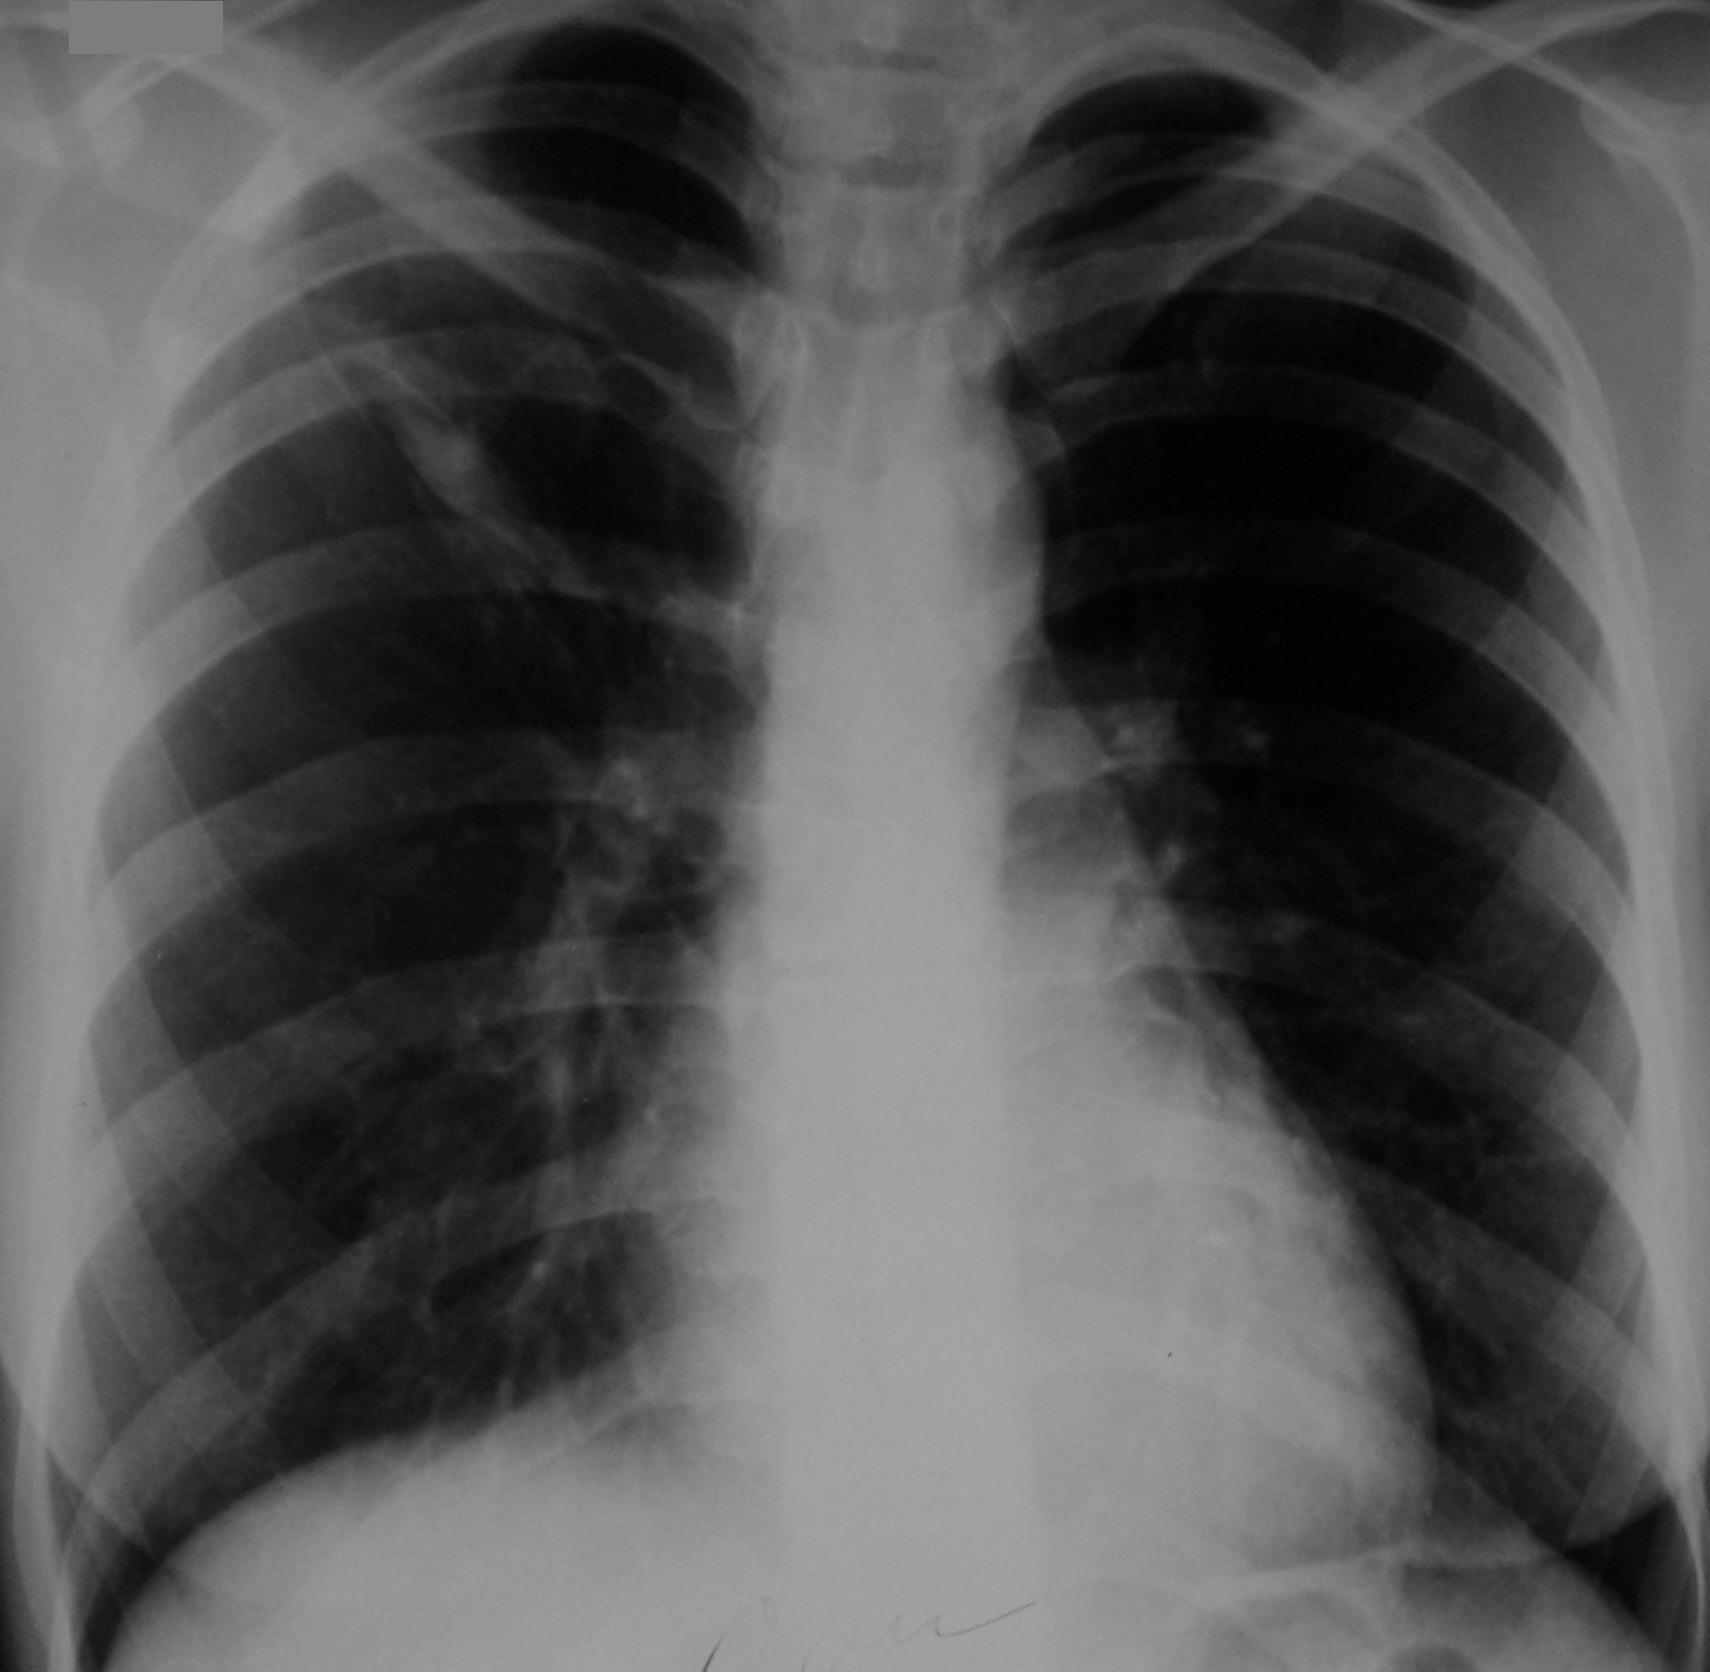

Рис. 3. Обзорная рентгенограмма и томограмма органов грудной клетки больной С., 24 года при поступлении, где:

а) прямая проекция;

б) боковая проекция;

Из анамнеза болезни выяснено, что инфильтративный туберкулез S2 правого легкого в фазе распада, МВТ отрицательно выявлен в августе 2004 г. (рис. 3).

В качестве химиотерапии получала изониазид, рифампицин, пиразинамид, этамбутол. В течение 3-х месяцев первой фазы лечения состояние больной улучшалось. При переходе на поддерживающее лечение 2-мя препаратами изониазидом и рифампицином состояние резко ухудшилось, появилась гипертермия до 38,6ºС, слабость, одышка при физической нагрузке и кровохаркание до 50 мл в сутки. Направлена на стационарное лечение.